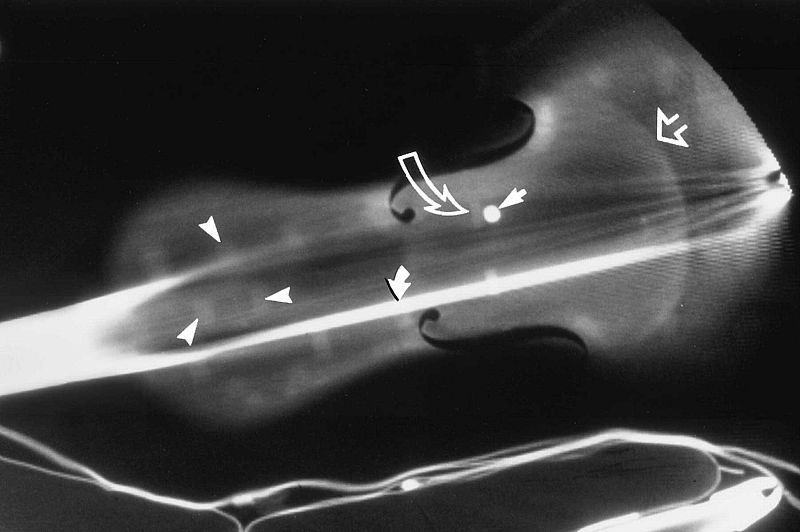

- Son instrumentos únicos y solo existen unos 650 en todo el mundo

- Científicos han reproducido uno usando la tomografía computerizada